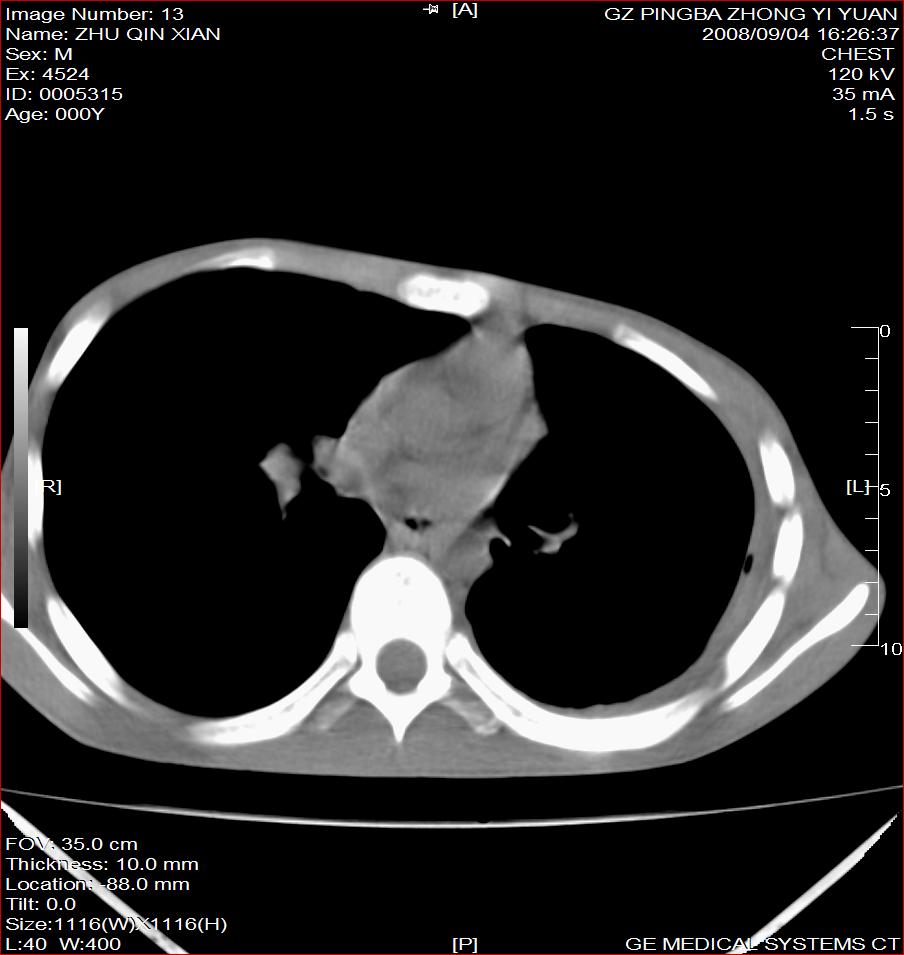

以下是引用随光逐影在2008-9-4 20:05:00的发言:[br]1)考虑两肺结核。2)左侧胸膜炎(胸膜肥厚、粘连,胸腔积液)。3)左侧局限性气胸。

以下是引用子十在2008-9-4 19:34:00的发言:[br]左上肺结核并空洞及双肺播散。节段性肺不张、胸腔积液、胸膜肥厚粘连。[br]